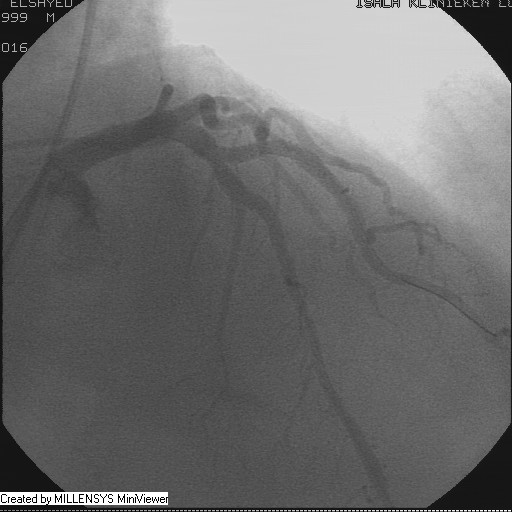

Patient transfered to Cardiac Catheterization Laboratory, coronary angiography showed atherosclerotic coronaries but without significant lesions, especially LAD that was patent with TIMI 3 flow (Figure 1- 5). Re-evaluation of the Angiography showed a small stump that can be for an occluded 1st diagonal (Figure 2a), at that level the LAD has a non-significant lesion.

Figure 4